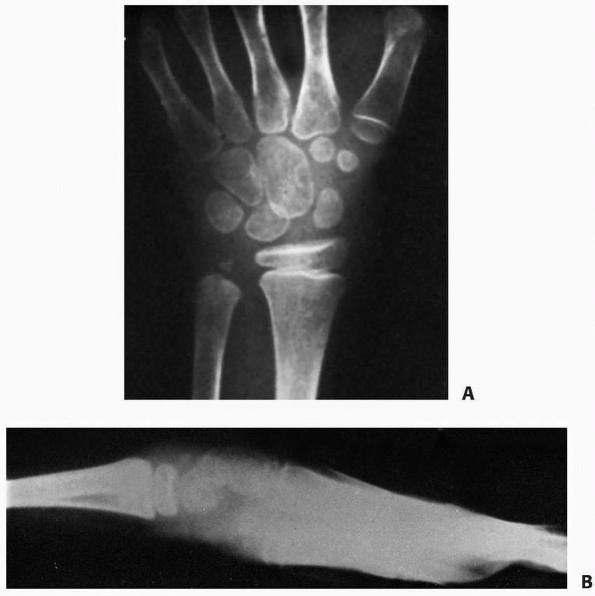

fractures of the metacarpal head are rare but occur most often in the

small ray.11,26,84,111 S-H II fractures of the small metacarpal are most common among patients 12 to 16 years of age.111,122,140

Intra-articular, head-splitting fractures at the metacarpal epiphysis

and physis consistent with S-H III and IV patterns seldom occur at the

metacarpal level but are problematic when displaced (Fig. 8-43).

most frequent site of metacarpal fractures in children. Neck fractures

in children are analogous to boxer’s fractures in adults (Fig. 8-44).

Neck fractures are more common in the small and ring fingers.

Fortunately, these injuries are juxtaphyseal and have considerable

remodeling potential.